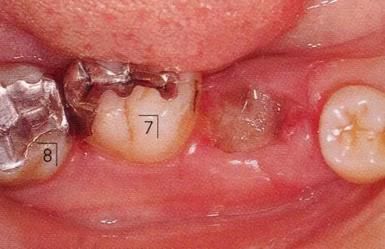

360截圖20170422101945505.jpg

▲圖9-1,2

▲圖9-1 預(yù)定進(jìn)行正畸治療的患者,下頜磨牙區(qū)的右下6,7牙根接近,并在右下7遠(yuǎn)中存在垂直性骨組織缺損。對(duì)牙體狀況、牙周組織、咬合情況進(jìn)行診斷后制定出的治療方案為:將右下6拔除,對(duì)右下7遠(yuǎn)中的骨組織缺失進(jìn)行再生療法。

▲圖9-2 同部位X光片。右下6遠(yuǎn)中存在牙根接近,較深的骨組織缺損以及II度根分叉病變,所以將其拔除。

360截圖20170422101957225.jpg

▲圖9-3

拔牙后1周的狀態(tài)。愈合后,預(yù)定進(jìn)行正畸治療穩(wěn)定牙列。